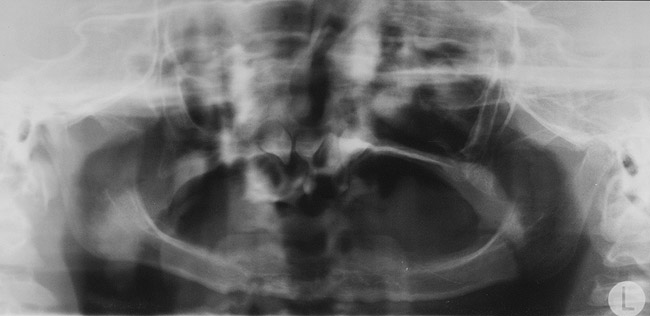

Figure 3  Pretreatment panoramic radiograph displaying the oligodontia and lack of alveolar bone development.

Figure 3